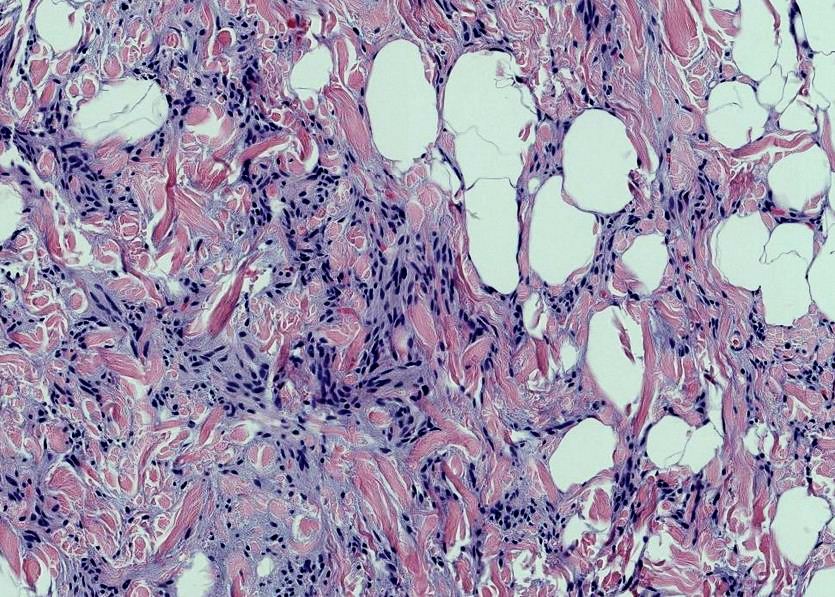

65 year old man posterior auricular neck deep dermal nodule. easy peezy?#dermpath #PathTwitter #dermatology Etan Marks, DO @ArjunRamaiya1 Lorand Kis Olaleke Folaranmi Tristan Rutland MBBS FRCPA IFCAP Trish Stratus Marcelasaeblima. Allison Osmond MD MSc FRCPC Ahmed Alomari, MD Gonzalo De Toro